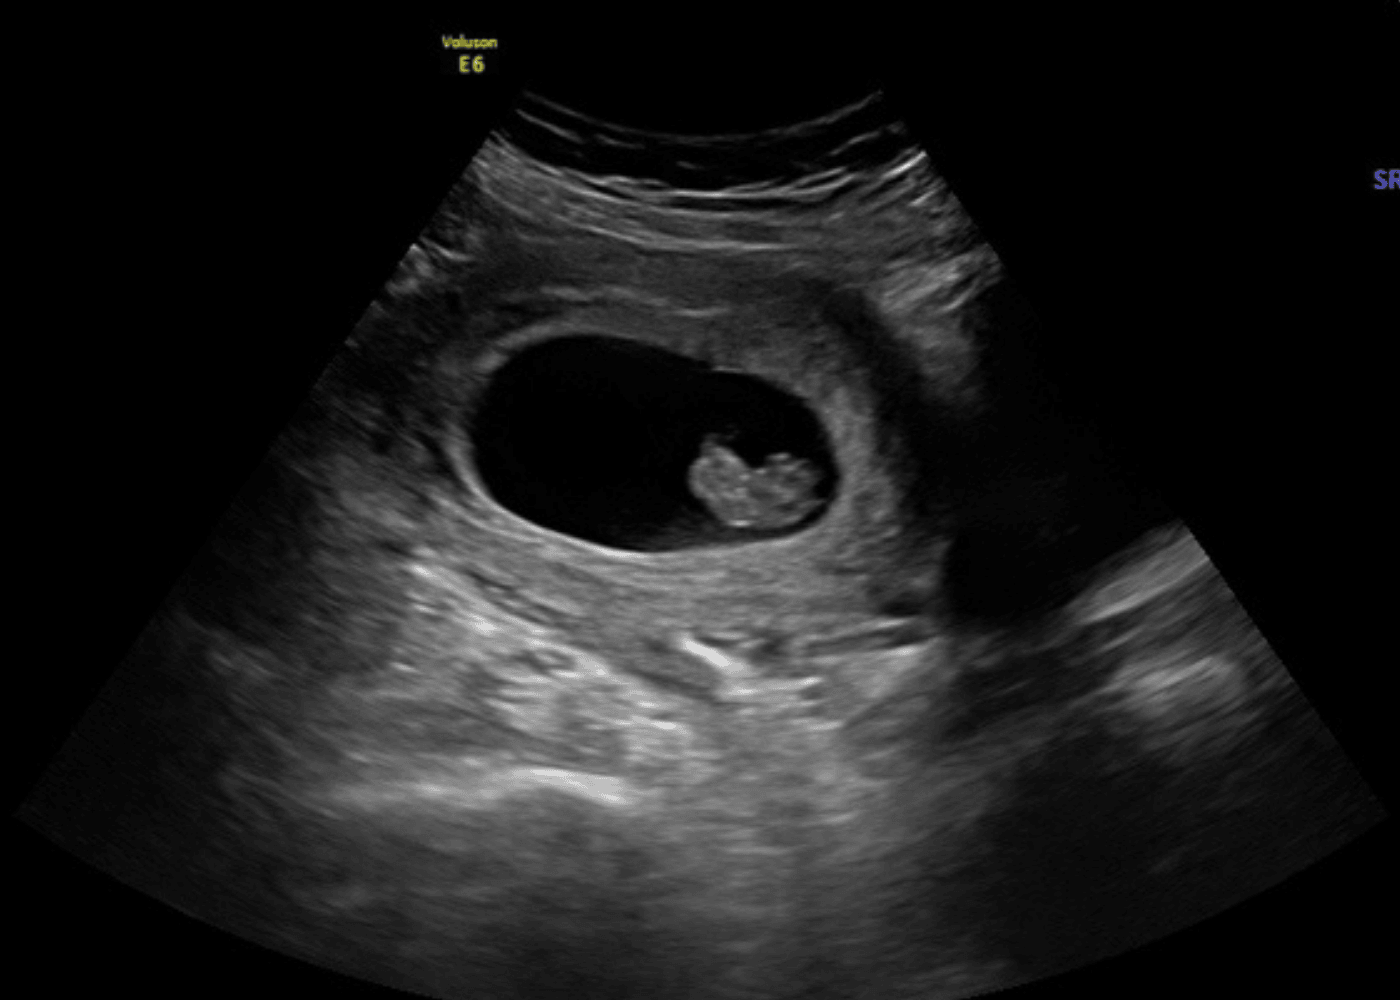

Ultrasound scan showing an early pregnancy with a developing fetus inside the gestational sac.

6–10 Weeks

Early Reassurance $75

A gentle, focused visit designed to confirm baby’s heartbeat during the earliest weeks of pregnancy.

These first weeks can feel tender and uncertain. This appointment offers a calm space to pause, see baby, and leave feeling reassured.

Includes approximately 5–10 minutes of 2D ultrasound imaging, along with:

• Heartbeat confirmation

• Basic measurements

• Confirmation of one baby

• 1–2 printed b&w keepsake images

• Transvaginal imaging if needed for clearer early views

Pregnancy dating calculators can sometimes be off by a few days, so if you are earlier than expected we’ll happily welcome you back for a brief return visit for $40.